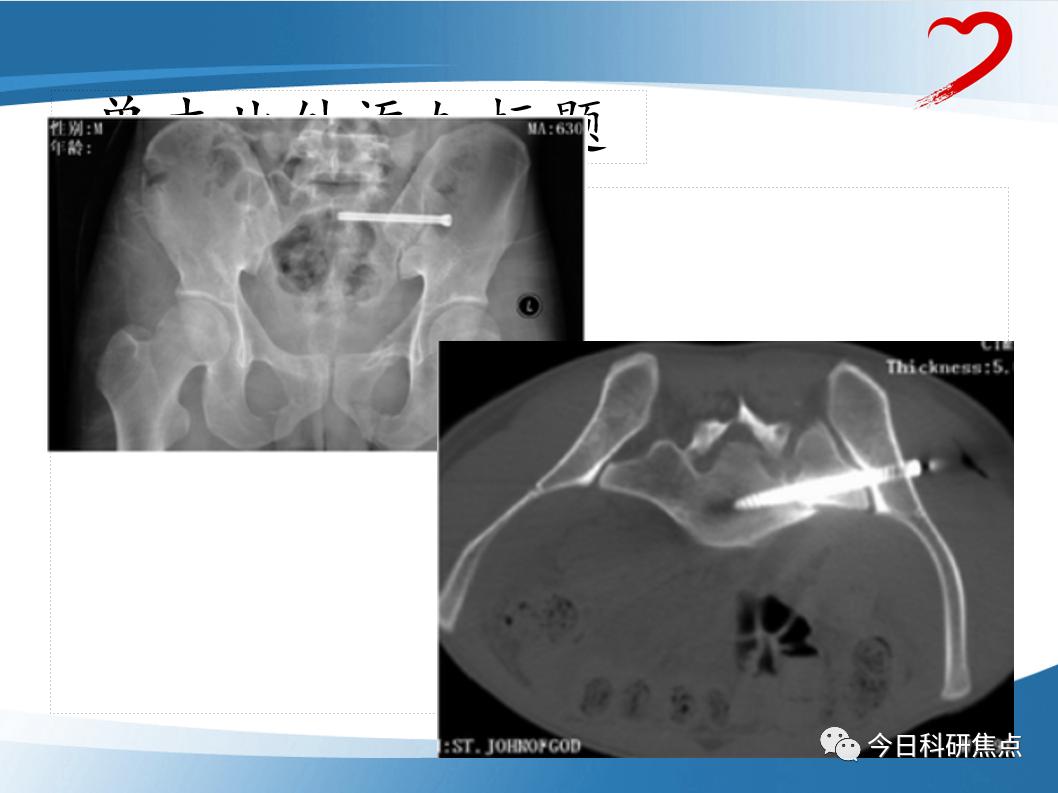

今天小樱桃给大家带来了 创伤骨科PPT ,让我们一起来学习一下吧~